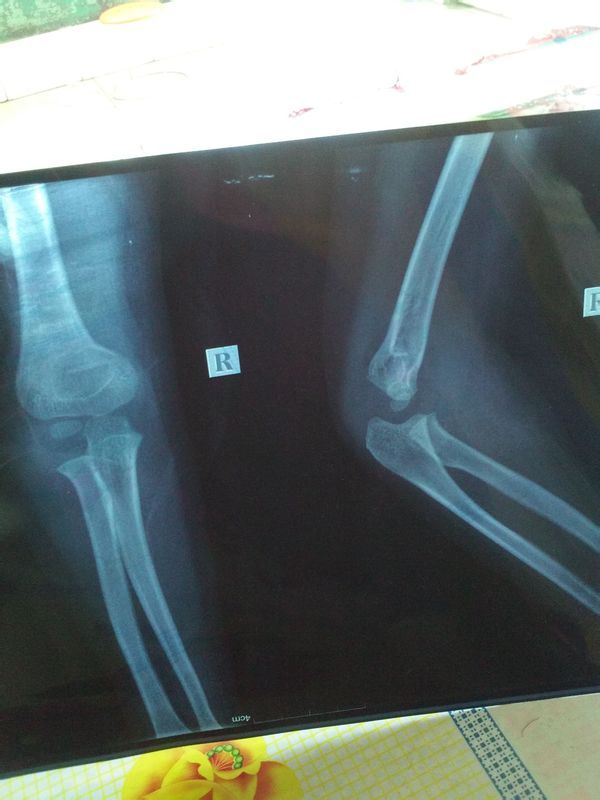

五周岁小孩胳膊肘轻微骨折 现在打上石膏了 多长时间复查一次 多长时间能拆掉石膏 孩子 快开学了 点击展开 匿名用户 2015-02-24 10:14 为您推荐: 其他回答 你好,根据你的提示,石膏外固定一般术后7天、14天到医院复查一次,以防骨折移位及石膏过紧,以后每个月复查一次。恢复时间较长。至少3个月可以试着去除石膏。切记不要自行去除石膏。 ū 2015-02-24 11:55 相关问题 我的小孩5岁,胫骨腓骨骨折现在快六十天了,请问可以拆掉石膏了吗?刚拆完石膏要注意什么? 我女儿5周岁在幼儿园上中班,星期天在家胳膊摔骨折了,到医院打了石膏也没有住院,学校买的有保险可以 小孩胳膊肘骨折4个多小时去医院,到医院打的石膏,现在成缺血性臂肌栾缩,就是肌肉萎缩,手成爪行手,这